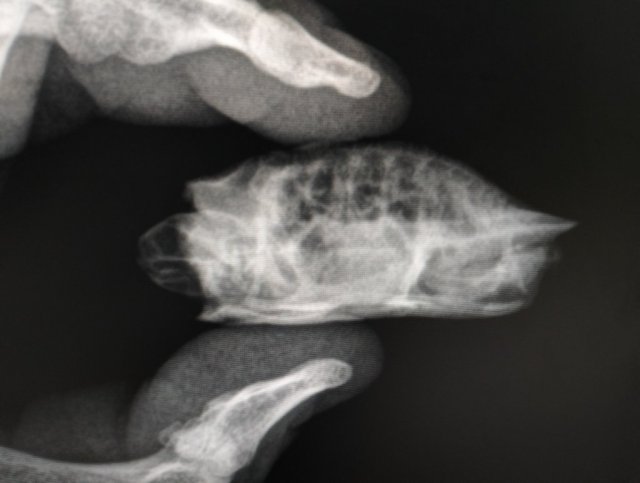

shieldorb Ваше имя: Андрей Локация: Оренбург,Россия Опубликовано: 5 декабря 2023 Опубликовано: 5 декабря 2023 Из какого вы города (области)? Ваш возраст? Вид черепахи? красноухая Где содержится (пол, аквариум, террариум, контейнер)? Размер жилища? аквариумКакой объем воды в литрах?120л Какое стоит оборудование? 4.1. Установлена ли лампа накаливания в качестве точки прогрева? Сколько часов работает в день?8,да 4.2. Установлена ли ультрафиолетовая лампа? Если да, то с каким спектром UVB%? Как называется и как давно установлена? Сколько часов работает в день?ночная ноунейм 4.3. Установлен ли берег? Что используется в качестве берега?пластиковый берег на липучке 4.4. Установлен ли фильтр для воды, если да, то какой, внешний/внутренний? Какая мощность?внутренний фильтр 200л/ч 4.5. Установлен ли нагреватель воды?да Имеется ли грунт в жилище черепахи? Если да, то какой?нет Какая температура в жилище черепахи (воздуха/воды)?водух 28,вода 26 Что черепаха ест и как часто? Какие даете подкормки и как часто?рептомин 1 раз в день Возраст, точный вес и длина панциря черепахи? В чём проблема/болезнь? Как давно проявилась?купили у цыган на рынке 4 месяца назад,вес 22г,длина 5 см.Мягкий панцирь,перестала есть и сопли немного из носа идут.Когда на суше лежит долго-панцирь белого цвета становиться Обращались ли в ветклинику? Как называется ветклиника? Как зовут врача (ФИО)? Вводились ли какие-то препараты, если да, то в каких дозировках? Что было сделано по рекомендациям врача?Были у псевдогерпетолога который гамавит назначил колоть,больше к нему не ходили после того как нашли инфу по лекарствам.По его рекомендациям кололи какой то красный витамин и белый(выписал и дал в руки два шприца сказал колоть внутримышечно 1 раз в день и гамавит ещё предложил купить самим)после уколов через какое то время вроде чепу стало легче но через 2 недели опять приуныл. Фото смогу приложить только завтра

Консультанты moth Ваше имя: Мария Локация: Москва Опубликовано: 5 декабря 2023 Консультанты Опубликовано: 5 декабря 2023 @shieldorb Вам нужно убрать и сейчас выключить эту чёрную лампу. Такие лампы (и та, что была для обогрева) могут фонить вредным ультрафиолетом, и вместе пользы наоборот нести вред. Как давно были у ветеринара? сколько дней не ест? есть возможность рентген ей сделать? не обязательно у герпетолога, в любой клинике, я объясню какие снимки нужны. Это чтобы понять в чём проблема - желудок или лёгкие (или всё сразу) Скорее всего у черепахи дефицит кальция из-за неправильной лампы. Лечится это уколами, по-другому никак. И Вам нужно заказать хорошую уф лампу. На ВБ есть Simple Zoo 10%UVB - закажите её. Для обогрева пусть стоит обычная накаливания. Но нужно, чтобы берег прогревался до 32 градусов

shieldorb Ваше имя: Андрей Локация: Оренбург,Россия Опубликовано: 5 декабря 2023 Автор Опубликовано: 5 декабря 2023 Может подскажите герпетогола в г. Оренбург,у нас по поиску обычные врачи которые не являются герпетологами но почему то берутся лечить видимо из жажды наживы. Поищем по поводу рентгена,лампу выключил,новую закажем.было две черепашки изначально брали для детей из за незнания черепашьей темы от слово совсем ,затем начали изучать .привезли к ветеринару одной совсем плохо было она почти не двигалась а вторая более менее это было полтора месяца назад где то.врач сказал что там где купили их изначально кормили неправильно и у них рахит,ток у одной совсем безвыходная ситуация а у второй поправить можно уколами и дал два шприца инсулиновых сказал колоть по по 0,5 УФ лампа E27 UVB 10.0 для рептилий от Simple Zoo, 13 Вт Simple Zoo https://wildberries.ru/catalog/165006555/detail.aspx такая?